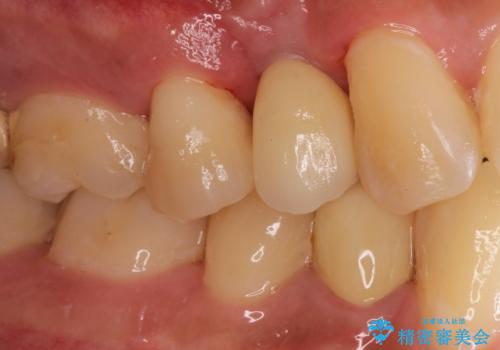

インプラントによる治療は隣在歯を削らずに咬合回復できるという利点があります。

セラミッククラウンにより自然な見た目で修復できました。